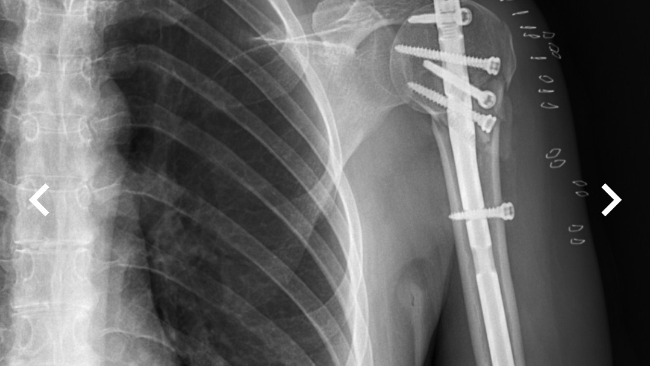

I underwent surgery at HCP Hospital in Poznań under the public healthcare system (NFZ). During the operation, my bone was stabilized with a metal rod and five screws, which gave my arm a chance to heal. I am currently waiting in a long queue for rehabilitation under the National Health Fund — my rehabilitation is scheduled for August 2026.

My arm also requires a second surgery, during which the screws will be removed. They turned out to be too long in relation to my slim arm structure and block the movement of my arm, making it impossible for me to lift it.